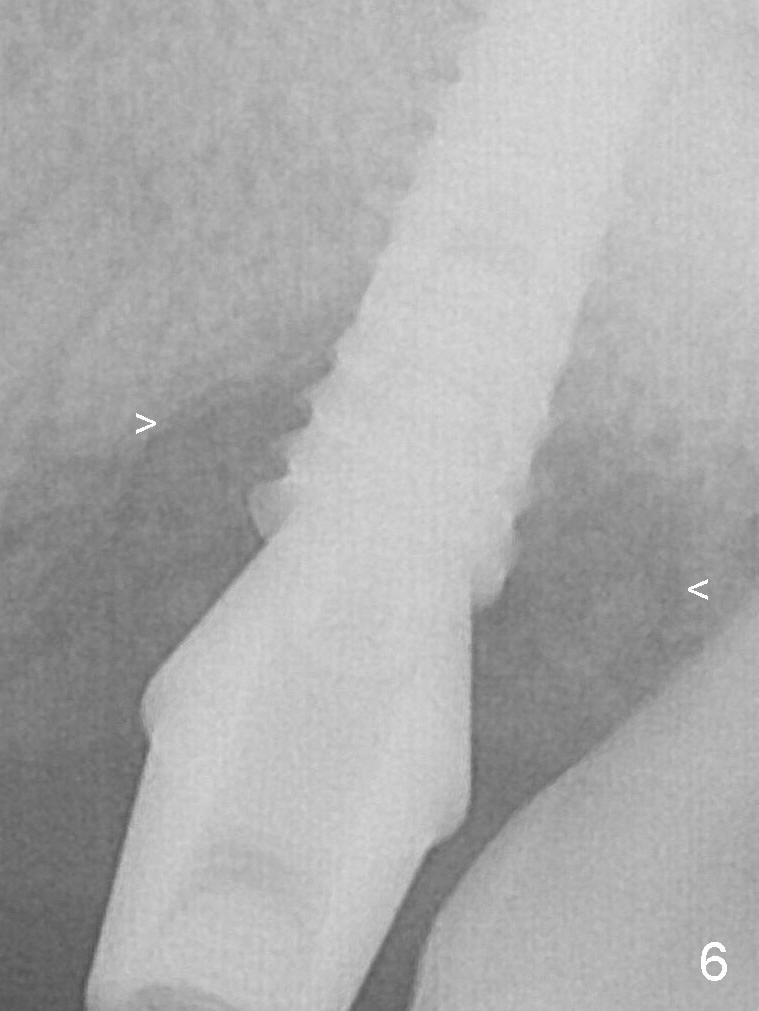

The amount of the bone graft mesial and distal the implant seems to reduce 3 and 4 months postop, respectively (Fig.6,7 arrowheads).  When the acrylic is cut off 4 months postop, the bone graft is loose.  The gingiva is unhealthy.  The abutment and implant are loose.  A healing abutment is placed (5x4 mm).